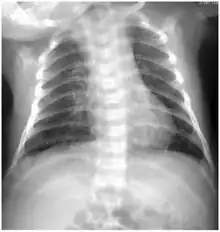

Under magnification of 50X, a McCoy cell monolayer culture, and that some of the cells exhibited Chlamydia trachomatis inclusion bodies. Using cell cultures from the McCoy cell line is one methods implemented in diagnosing Chlamydia infections. -

Chlamydia trachomatis inclusion bodies (brown) in a McCoy cell culture